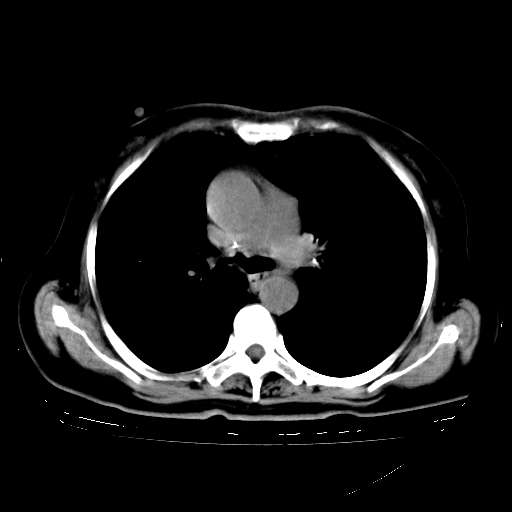

标题: CT23067:女,70岁,咳嗽、咳痰一个月,低热一周。 [打印本页]

女,70岁,咳嗽、咳痰一个月,低热一周。

1、右肺占位,考虑周围型ca 。

2、右下肺软组织密度肿块影,考虑肺隔离征。

3、两肺肺结核(右肺下叶背段及左肺)。

4、主动脉夹层。

5、右侧少量胸腔积液。